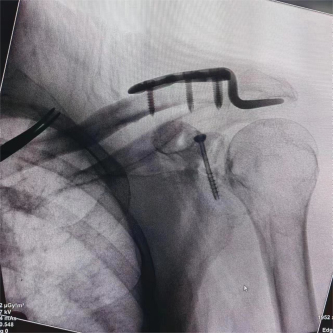

(术中影像)

患者因交通事故致伤导致左肩关节盂骨折及左肩锁关节脱位和右尺桡骨骨折,骨折移位明显,疼痛剧烈,具备手术指征。但患者为75岁高龄,基础疾病多,担心患者无法耐受过大的手术创伤。经术前讨论,创伤外科中心张立峰教授团队决定为患者应用骨科手术机器人辅助经皮内固定治疗肩关节盂骨折的手术方案。术中,通过机器人进行采集数据、并规划手术等人工智能操作,仅用1cm切口即成功完成手术。